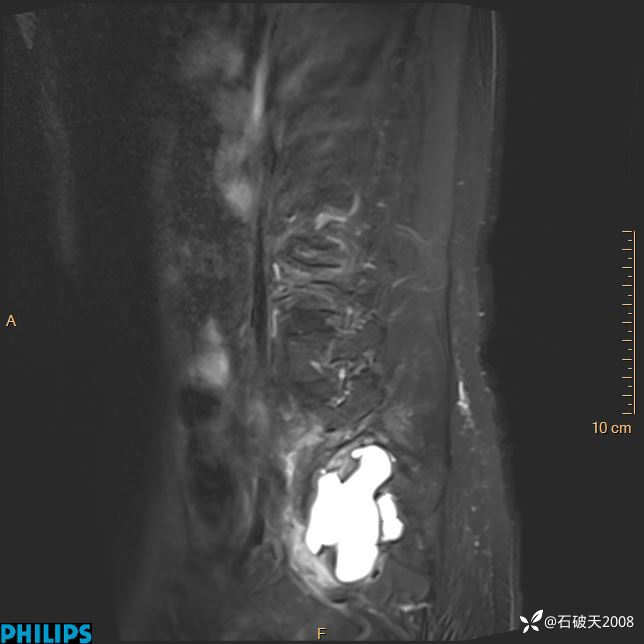

2023年3月份MRI影像

T2矢状位压脂